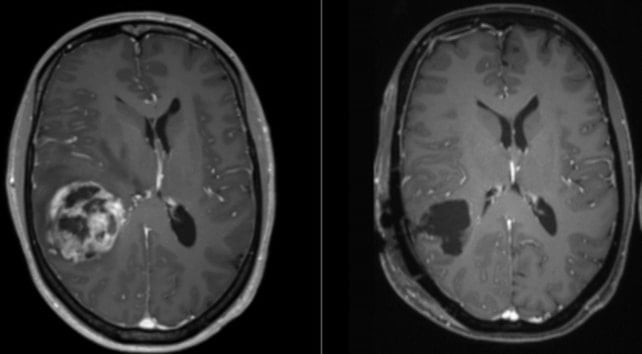

الجراحة هي حاليًا المرحلة الأولى من علاج الورم الأرومي الدبقي. (Ars Neurochirurgica/Wikimedia/CC 4.0)